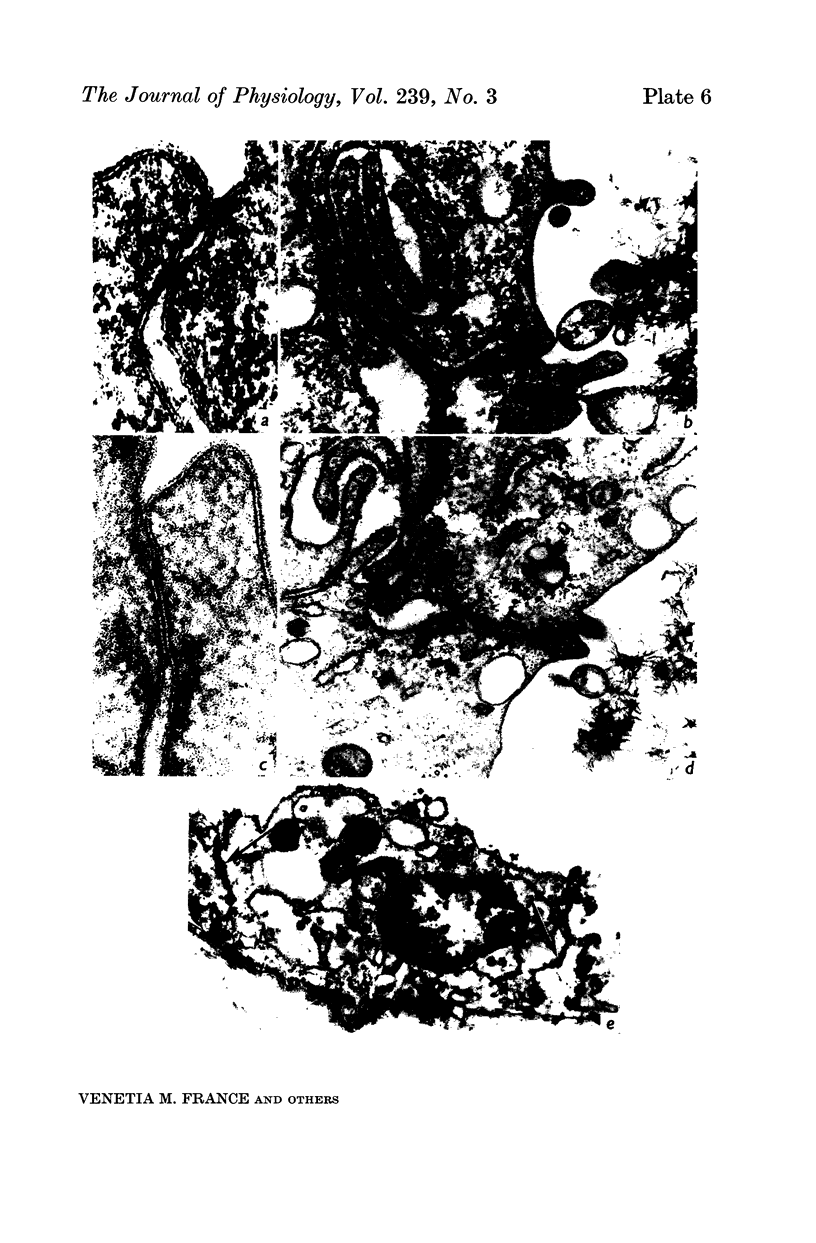

2. The development of tight junctions between the bladder epithelial cells was investigated by incubating the tissue with solutions containing 1 mM-LaCl3 on the mucosal surface. No penetration of the junctions by lanthanum was observed in foetuses of 90 days or older. In younger bladders, the epithelial layer was stripped by treatment with lanthanum, but tight junctions appeared to be fully developed in early bladders incubated without lanthanum.

3. The surface structure of the luminal (mucosal) plasmalemma was fully developed at 50 days.

5. Antidiuretic hormone (ADH) had no effect on net water movement but reduced the net efflux of sodium so that the flux ratio became 1·285 ± 0·255 (S.E. of mean) n = 8. ADH also had a striking effect on the structure of the epithelium, causing marked swelling of the intercellular spaces. The tight junctions remained an effective barrier to lanthanum penetration under these conditions; lanthanum was not observed in the enlarged spaces.